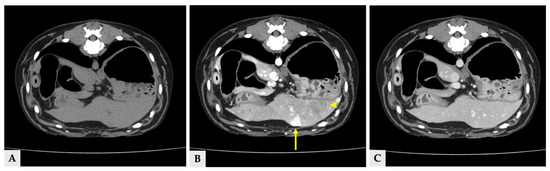

Multiple hyper- and hypoattenuating hepatic nodules were scattered throughout the liver parenchyma (maximum size 11.4 mm × 11.9 mm × 10.8 mm) (Figure 3), and numerous small splenic nodules exhibiting on pre-contrast and portal phase were also observed (Figure 4). Additionally, a soft-tissue mass was detected at the esophagogastric junction. Cervical ultrasonography revealed three distinct, heterogeneous right thyroid masses, with the largest mass demonstrating prominent vascularity on Doppler evaluation (Figure 5).

Figure 4.

Transverse CT images of splenic nodules at the same anatomical level. (A) Pre-contrast image showing splenic nodules that are isoattenuated relative to the surrounding splenic parenchyma. (B) Portal phase image at the same level demonstrating hyperattenuated splenic nodules (arrows). (C) Delayed phase image at the corresponding level, in which the splenic nodules show attenuation similar to or slightly higher than the surrounding splenic parenchyma.